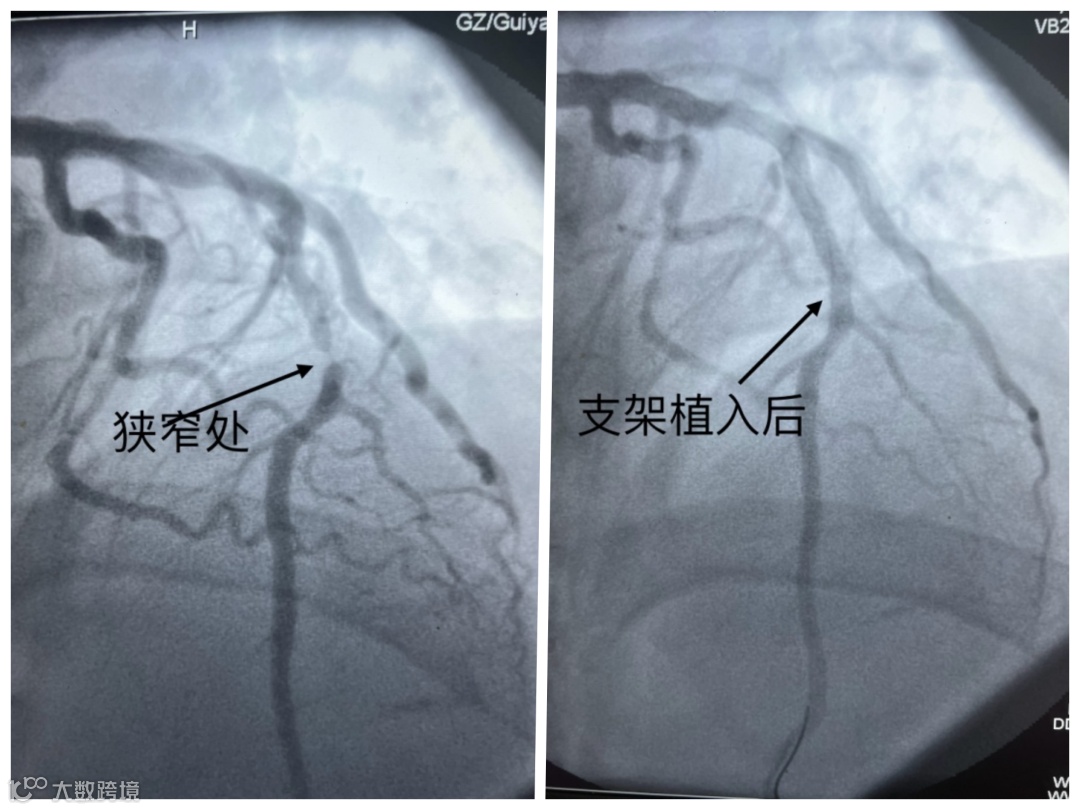

医生为其进行心电图检查,结果提示急性广泛前壁心肌梗死。随后,医生在其狭窄血管处植入支架,李先生转危为安。